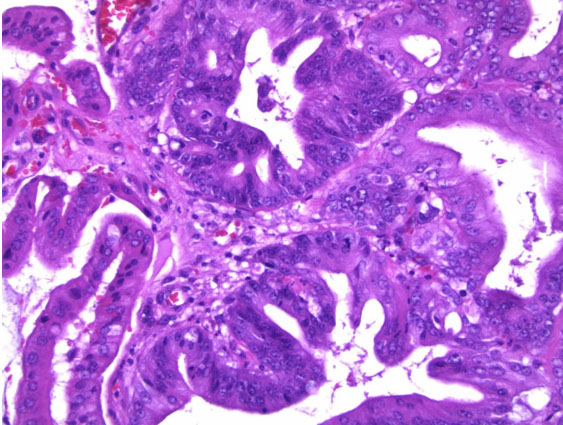

The GB was submitted to pathology for examination. Gross inspection demonstrated an intact saccular GB measuring 5.5 × 2 × 1.5 cm, without mural perforation. The GB lumen contained viscous green bile; no obstruction of the cystic duct or intraluminal calculi were seen. The GB wall was thin, without hemorrhage, significant inflammation, or edema. There was a 1.5 cm soft tan exophytic mucosal mass present within the body of the GB. Histological sections taken from the GB wall, cystic duct margin, and the mass demonstrated a complex adenomatous epithelial proliferation with a tubulopapillary growth pattern and intestinal-type differentiation. There was patchy accentuated cytologic atypia and glandular irregularity, consistent with high-grade dysplasia (Figure 3 and Figure 4). There was no evidence of stromal infiltration present to suggest invasive malignancy. The cystic duct margin was uninvolved by dysplasia. Based upon these findings, a diagnosis of ICPN with high-grade dysplasia was reported.

Figure 4: High magnification (200×) view of hematoxylin and eosin-stained section from lesion showing focal high-grade dysplasia in lesional glands in center of image, characterized by rounded nuclear contours, prominent nucleoli, frequent mitotic figures, and early cribriform architecture. Histological features of invasive malignancy were absent.